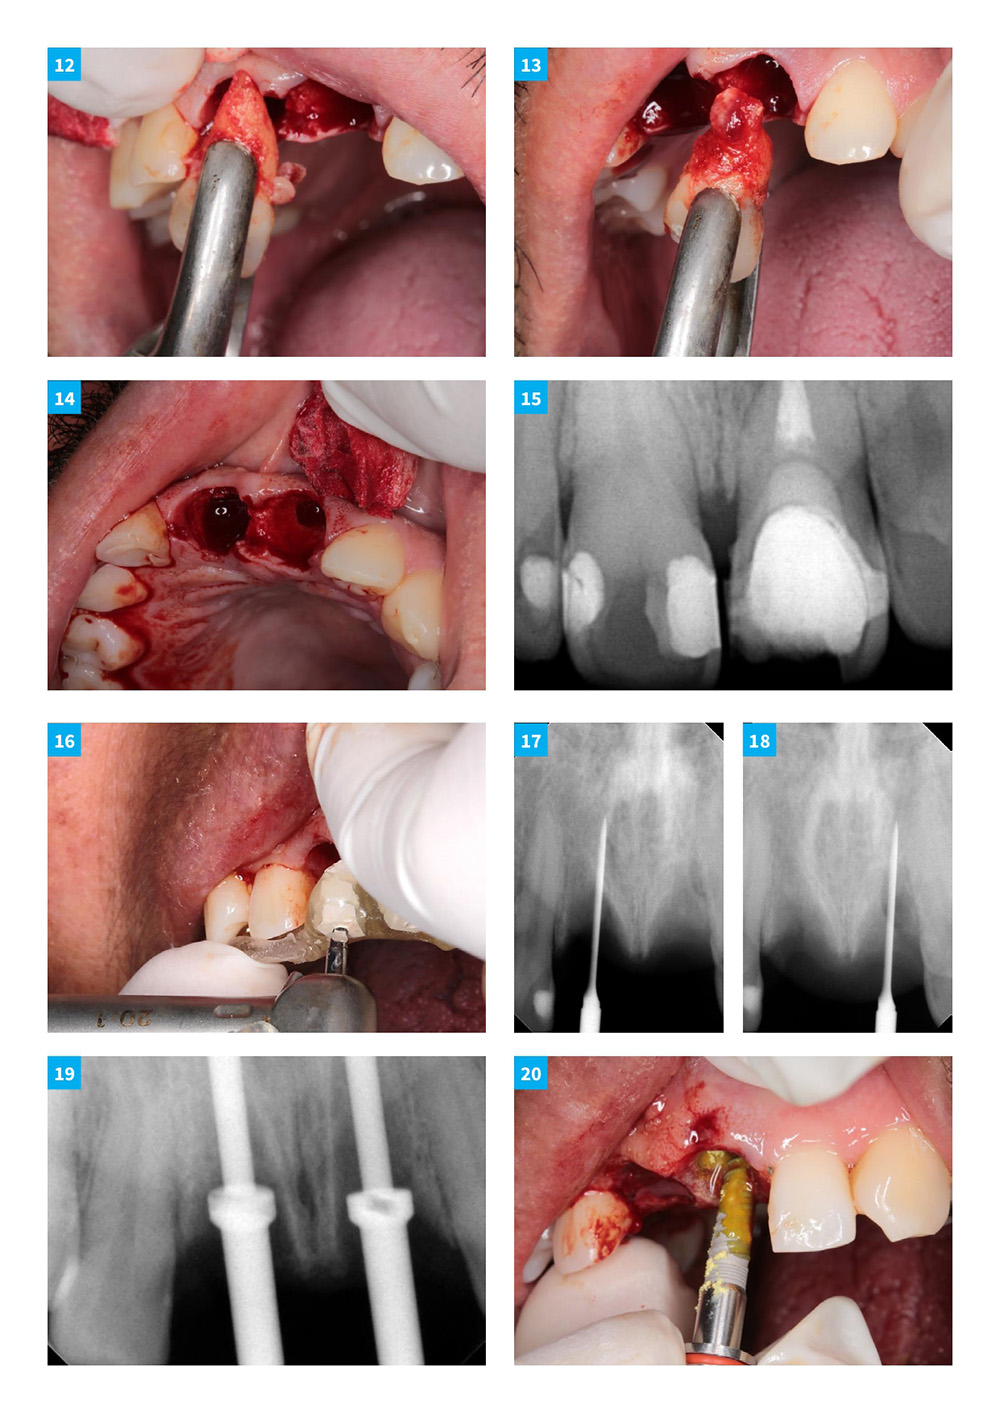

Anterior Central Teeth Extraction With Immediate Implant Loading: Multi-unit Bridge